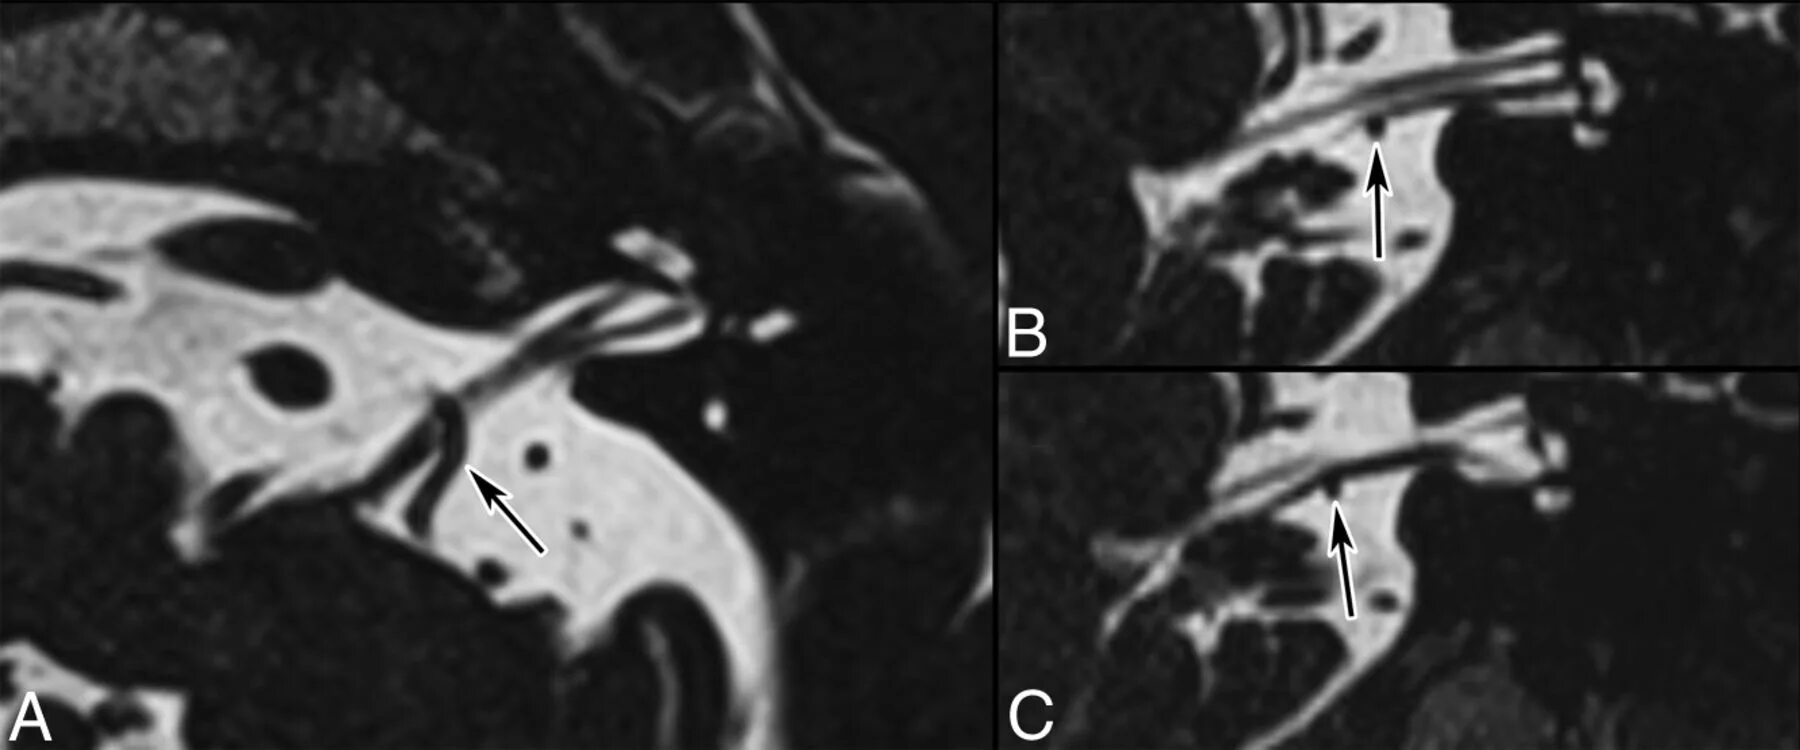

Нейроваскулярный конфликт нерва